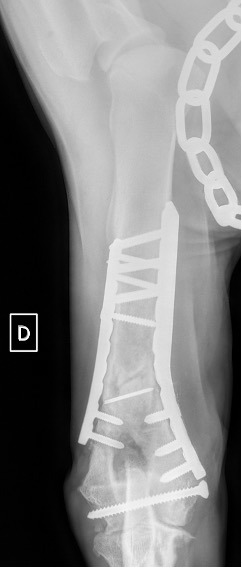

L’avènement récent des plaques anatomiques constitue une nouvelle option dans le traitement de ces fractures : dans l’exemple 3 (chat Ragdoll), une plaque anatomique médiale de 2 mm acceptant des vis de 1,6 et 2 mm a été utilisée seule avec succès.

Exemple 3 :

Figure 11 : Post-Op Immédiat

Figure 12 : Post-Op 1 mois